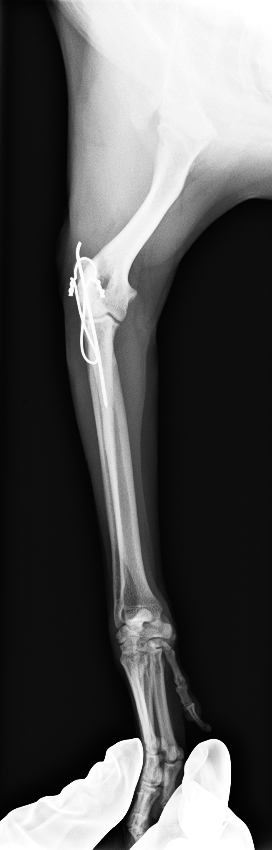

髄内ピン、テンションバンドワイヤーによる固定

after